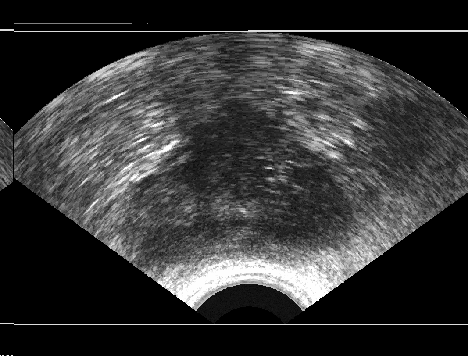

It is a challenge to validate any approach to segmentation. One has to measure the accuracy of the segment against ground-truth images. Ideally, if we have many users available to segment images, we can build “consensus segments”, or gold standard, to make more reliable measurements. Of course, this is usually not feasible with real images, for which there is no gold standard. Hence, we generated synthetic images whose gold segments were known a priori. For this reason, we used synthetic images that simulate transrectal ultrasound (TRUS).

TRUS images of prostates may be used to both diagnose and treat prostate diseases such as cancer. Starting with a set of prostate shapes , we created random segments through combinations of those priors, adding noise along with random translations and rotations, and we distorted the results with speckle noise and shadow patterns. Each image is thus created from its gold . Consequently, we can simulate user delineations by manipulating via scaling, rotation, and morphological changes, and we can simulate edits by running active contours with variable user-simulating parameters. The variability of user delineations was simulated according to several factors: error probability (), anatomical difficulty ( out of ), and the scaling factor for morphology (form to ). The user was modelled according to the level of experience (a random number from ), the user’s attention (a random number from ), and the user’s tendencies in terms of the segment size (a random number from ), whether tending to draw contours that are relatively small () or large ().

We generated 500 images from their corresponding gold-standard images111All images and their segments are available online: http://tizhoosh.uwaterloo.ca/. Furthermore, we generated 20 different segments for each image, assuming that there were 20 users. Figure 4 shows five examples of real and synthetic TRUS images. One should bear in mind that the purpose here was not to simulate the images realistically, but rather to have a base from which to generate variable segments from a perfect segment. Figure 5 shows an example of the gold segments and simulated user contours. The variability, coupled with the gold segment, is what is needed in our experiments.